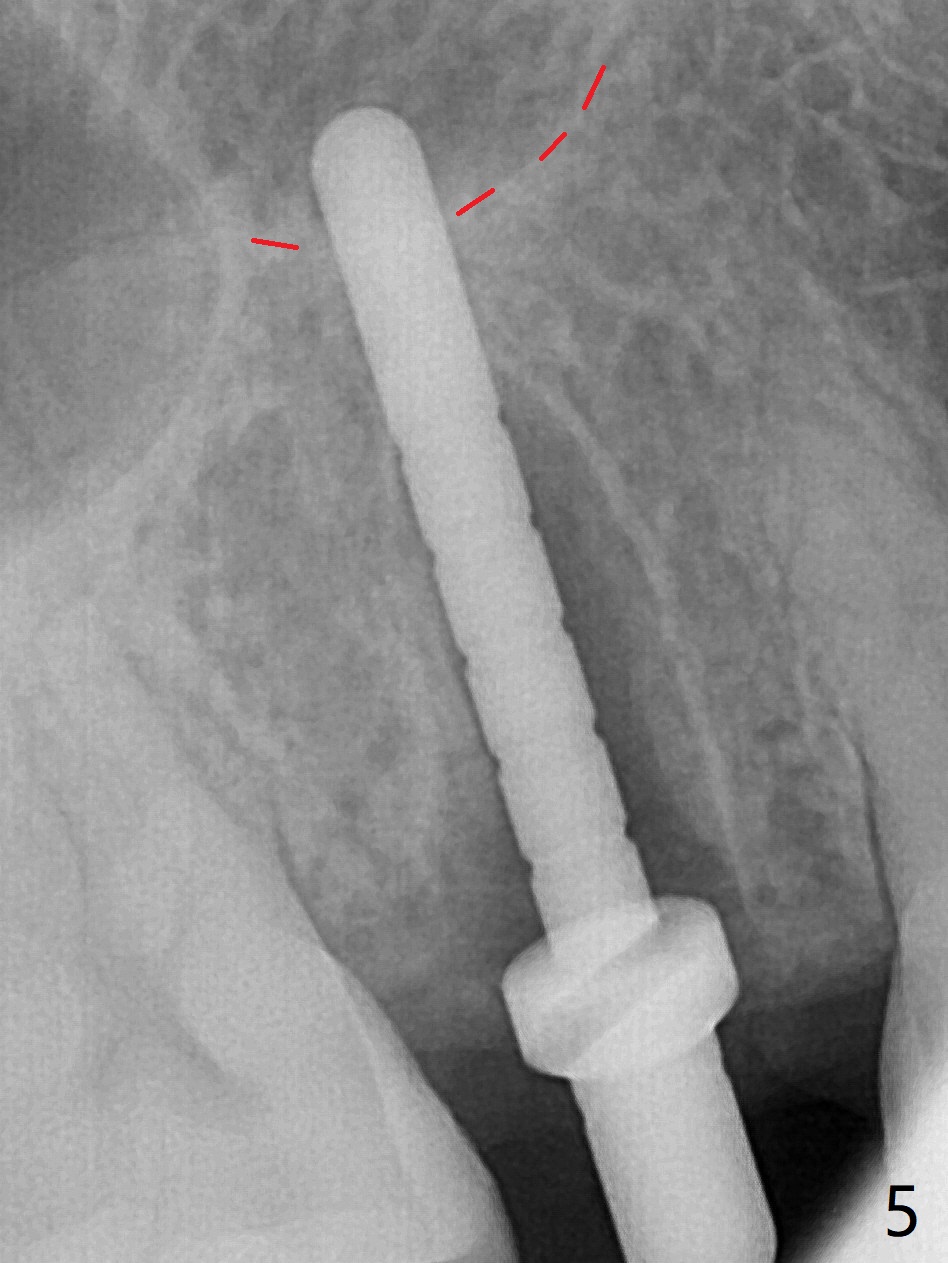

4号牙残根(图一)无创伤拔除使用一种叫做proximators牙周刀(periotomes,图二,三)。初期钻洞方位尚可(图四,五),植入3.8x15毫米植体,扭力50Ncm,修复成品基台完全就位(图六,七),植体,基台周围间隙填入骨粉(用血液调袢)后,制备基台(图八)和临时牙冠。